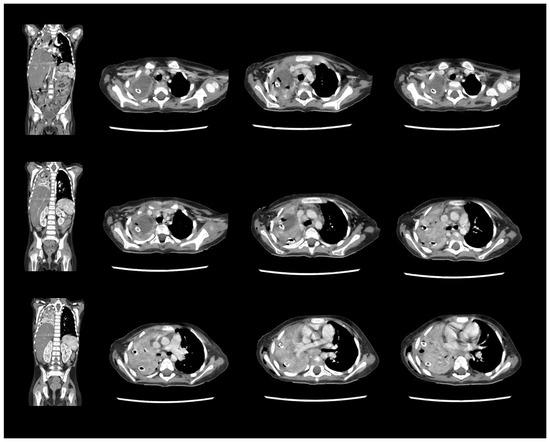

A Rare Case of Rhizomucor pusillus Infection in a 3-Year-Old Child with Acute Lymphoblastic Leukemia, Presenting with Lung and Brain Abscesses—Case Report

Invasive Mucormycosis (IM) is an extremely rare infection with a high mortality rate, caused by a group of fungi classified as Mucorales moulds. Rhizomucor pusillus is a saprophitic, thermophilic, and angioinvasive microorganism that grows and lives at about 45 °C and is usually found in different environmental spaces such as soil, air, water, food, and other organic matter. These features predispose the infection to wide dissemination, especially in immunocompromised patients and most often in children after chemotherapy for hematological malignancies (HMs). Mucormycosis in patients with hematologic malignancies and neutropenia represents between 0.07% and 4.29% of the concomitant diseases. IM can develop into an infection in different sites, but its most common manifestation is pulmonary, followed by rhino-orbital–cerebral and disseminated forms. In recent years, an increased morbidity rate has been associated with the ongoing COVID-19 pandemic, as cited in the literature. There are many publications with COVID-19-associated mucormycosis (CAM) cases. The present treatment protocol includes extensive and radical surgical debridement and systemic antifungal therapy with Liposomal Amphotericin B (L-AmB), Posaconazole, and Isavuconazole, either combined or as monotherapy. Despite these new treatment modalities, the mortality rate remains over 50%. We present a rare case of a 3-year-old child with acute lymphoblastic leukemia (ALL) and systemic Rhizomucor pusillus infection, diagnosed on the occasion of lung and brain abscesses. The patient underwent lung and brain surgery and is recovering well with no further complications. The two-year follow-up period shows no signs of recurrence of the disease. Full article

Show Figures

Figure 1